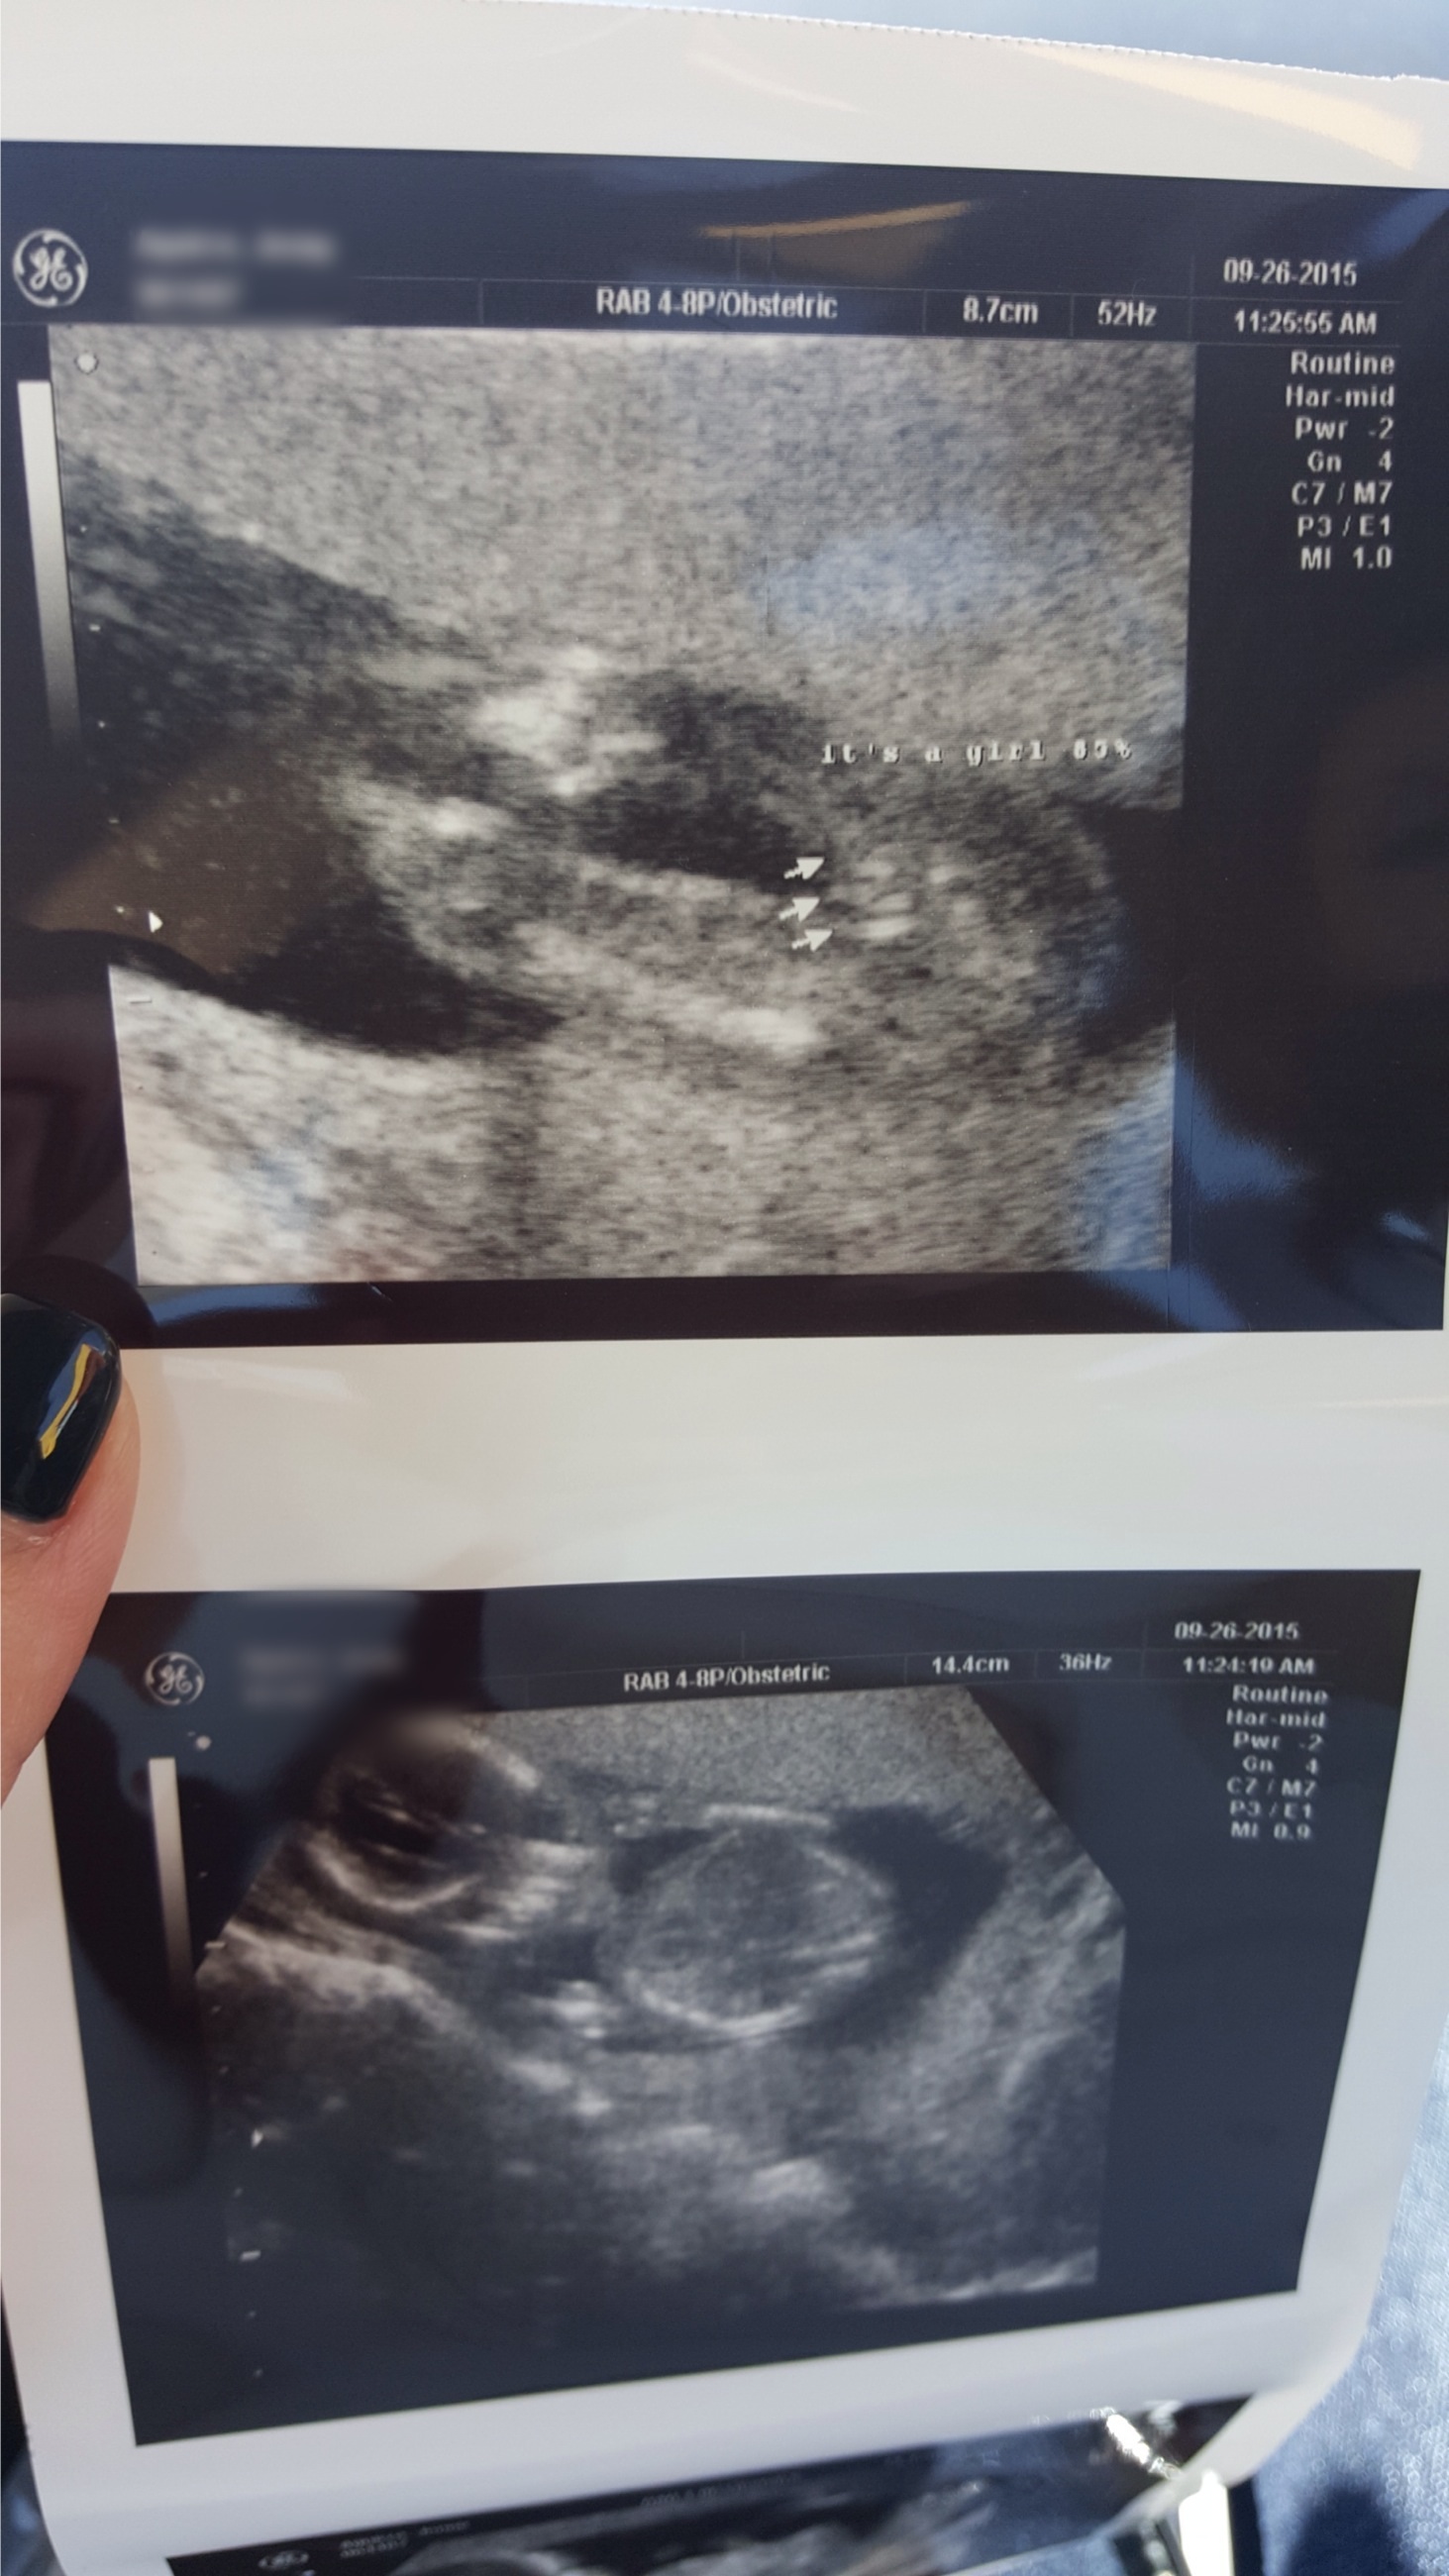

I say this with concern for your safety: your identifying information is visible. I've blurred it for you below. Please consider saving this version & replacing the photo in your OP. Creepers & sickos be lurking!

That looks like a girl to me but why would your technician only say 85%? Did they tell you come back another day to see if they can get a better look to be 100% sure?

ETA: all your personal info is on those pics.

1. There is personal information on those photos.

2. How would we know if that's right? Most of us are not ultrasound technicians or doctors.

3. It's not really polite to post photos of your baby's genitalia on a public forum.